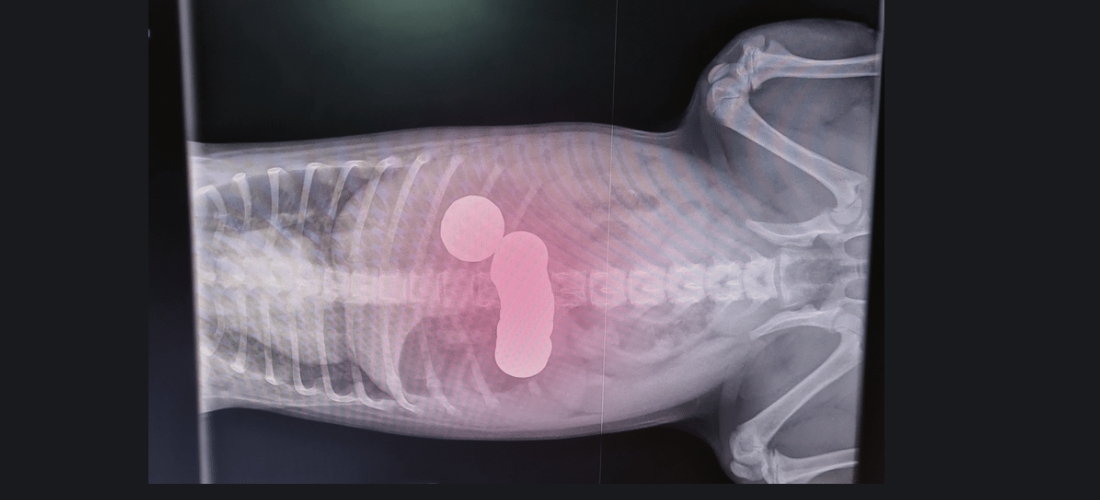

Upon examination, vets could see Daisy’s tummy was causing pain, which raised suspicions of a blockage. She was sedated and X-rayed for further analysis.

The PDSA team were stunned, as X-rays revealed several coins sitting in her stomach. Daisy underwent urgent surgery to remove them, while Ivana, her partner, and their two children waited anxiously at home for news.

During the operation, the vet team removed twenty coins from her stomach, including thirteen 1ps, three 5ps, two 20ps and two £1 coins. Daisy had swallowed a total of £2.68.